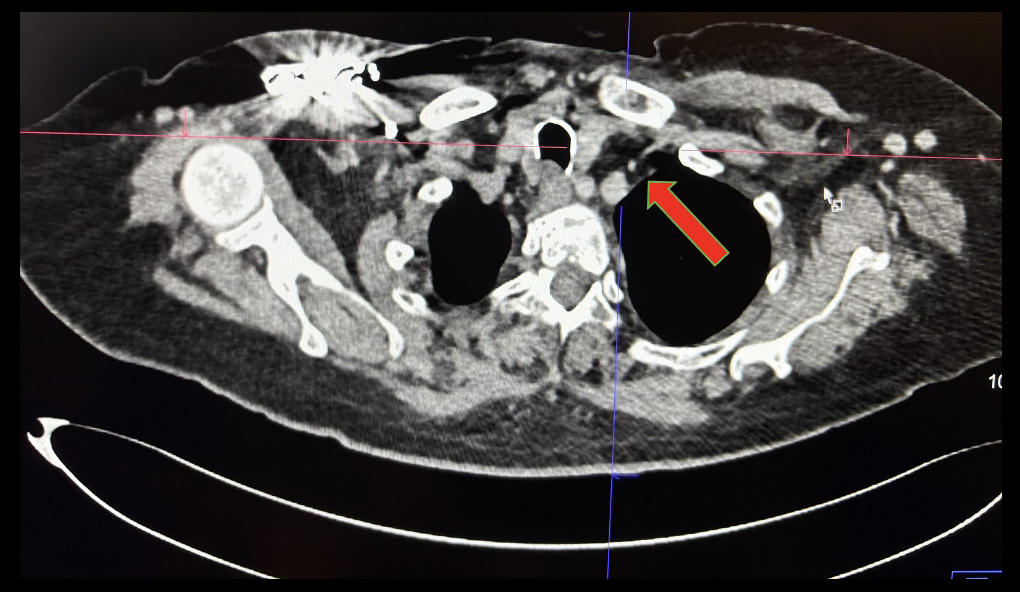

Chest CT venography revealed apparent narrowing of the left subclavian vein (red arrow) just proximal to where it crosses the first anterior ribDuplex Study of the Arteriovenous graft, left brachioaxillary graft noted patent AV fistula with computed flow rate of 2509 mL/min at the mid graft. No evidence of hemodynamically significant stenosis and thrombosis; Honeycombing pattern suggestive of subcutaneous edema